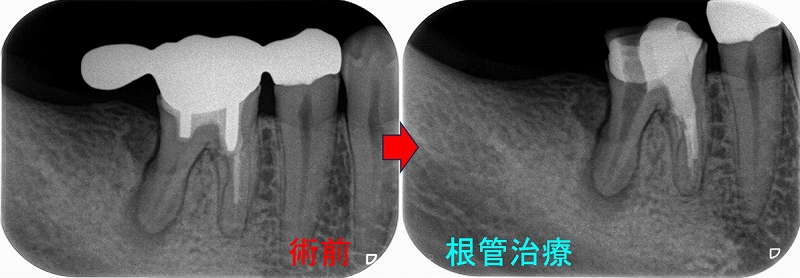

この部位は

以前、延長ブリッジが入っていた歯

5年後

遠心根に透過像が出てきており、歯茎からは膿が出てきていました。

日本の根管治療の約6割には問題があるというはあながち間違いではないと思います。

とりあえず根管治療をして治すことにしましたが、

近心根にはパフォーレーション 手付かずの遠心根には破折線が見られ、

患者さんにどうします!?遠心根はまず残せない、近心根は残すことが出来るがパフォーレーションの位置的に長く持たない可能性がある。

不思議なんですが、遠心根は根管治療していないにも関わらず折れてきている。

イメージ的に根管治療を行い中を削って歯を弱体化させている近心根が折れるならまだ分かるのですが・・・

患者さんと話し合い、近心根はヘミセクションをして残す 遠心根は抜歯

右下7の所には親知らずの移植と計画をしました。